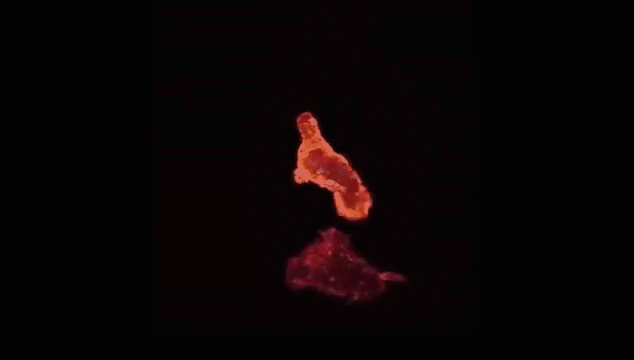

“天然杀伤”NK细胞率先吹响战斗号角,以癌细胞头部为突破口发起进攻,癌细胞负隅顽抗。

NK细胞头部部队成功突破,大部队快速抵达战场,癌细胞瞬间瓦解。

癌细胞失去战斗力,被NK细胞消灭。